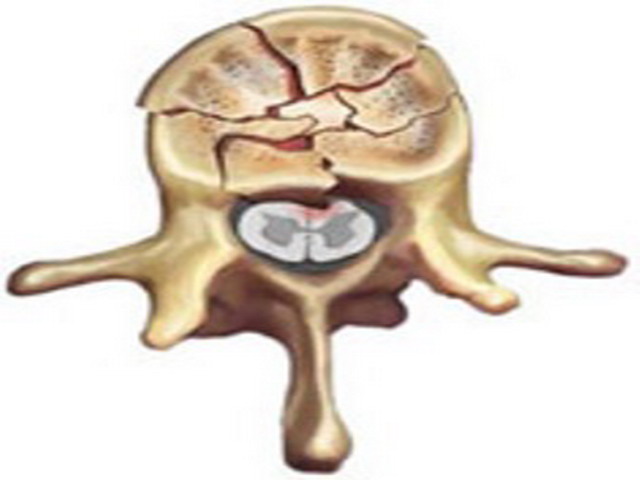

Травма позвоночника – это различные переломы, вывихи, травматические смещения позвонков, повреждение связок и межпозвонковых дисков, которые приводят к нарушению опорности и стабильности позвоночника и к сдавлению нервных структур (спинного мозга и его корешков). Поэтому травма позвоночника часто приводит к длительному лечению, нарушению качества жизни, к инвалидности, а порой и создает угрозу для жизни.

Компьютерная томография перелома позвонка.